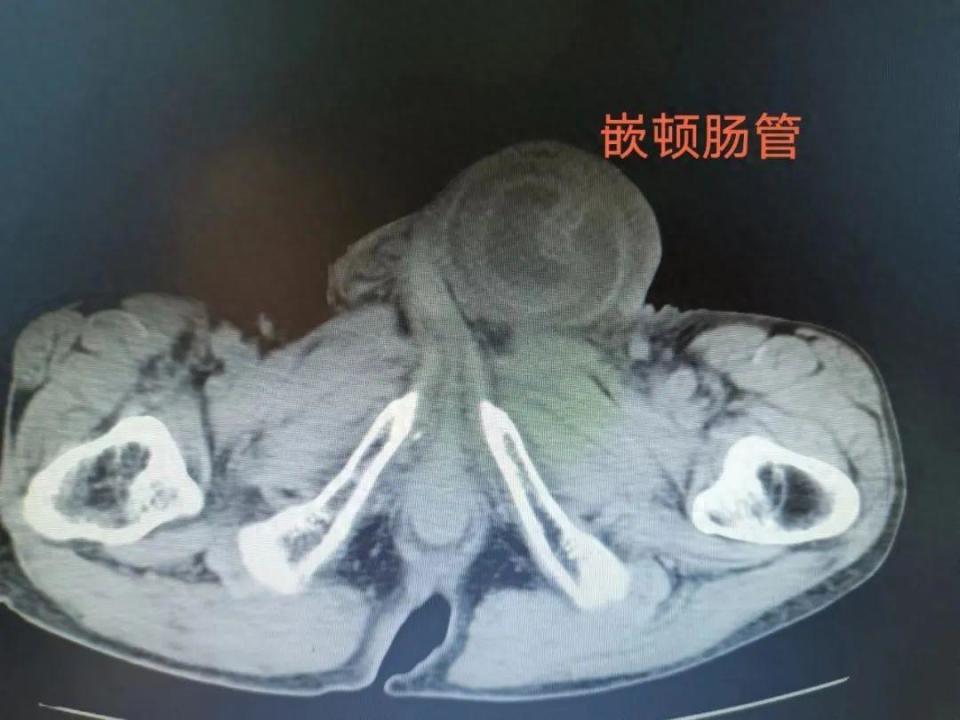

近日,90岁的刘爷爷(化名)感到腹部疼痛不适,伴恶心,呕吐不止,腹痛逐渐加重,家人随后陪同刘爷爷来到石门县中医医院外一科就诊,不能忍受的持续剧痛让患者备受煎熬,加上几十年的冠心病、肺气肿等已让老人奄奄一息,经完善检查,诊断为嵌顿疝合并肠梗阻。

长时间肠嵌顿最容易导致肠坏死、肠穿孔,此时患者心率116次/分,血压最低73/46mmHg,贫血、低蛋白血症,随时可能危及生命。

术中见小肠嵌顿于内环口中,肠管卡压伤及水肿明显,浆肌层破损肠壁呈黑色,肠管扩张粘连成团,幸亏手术及时,挽救了患者生命。